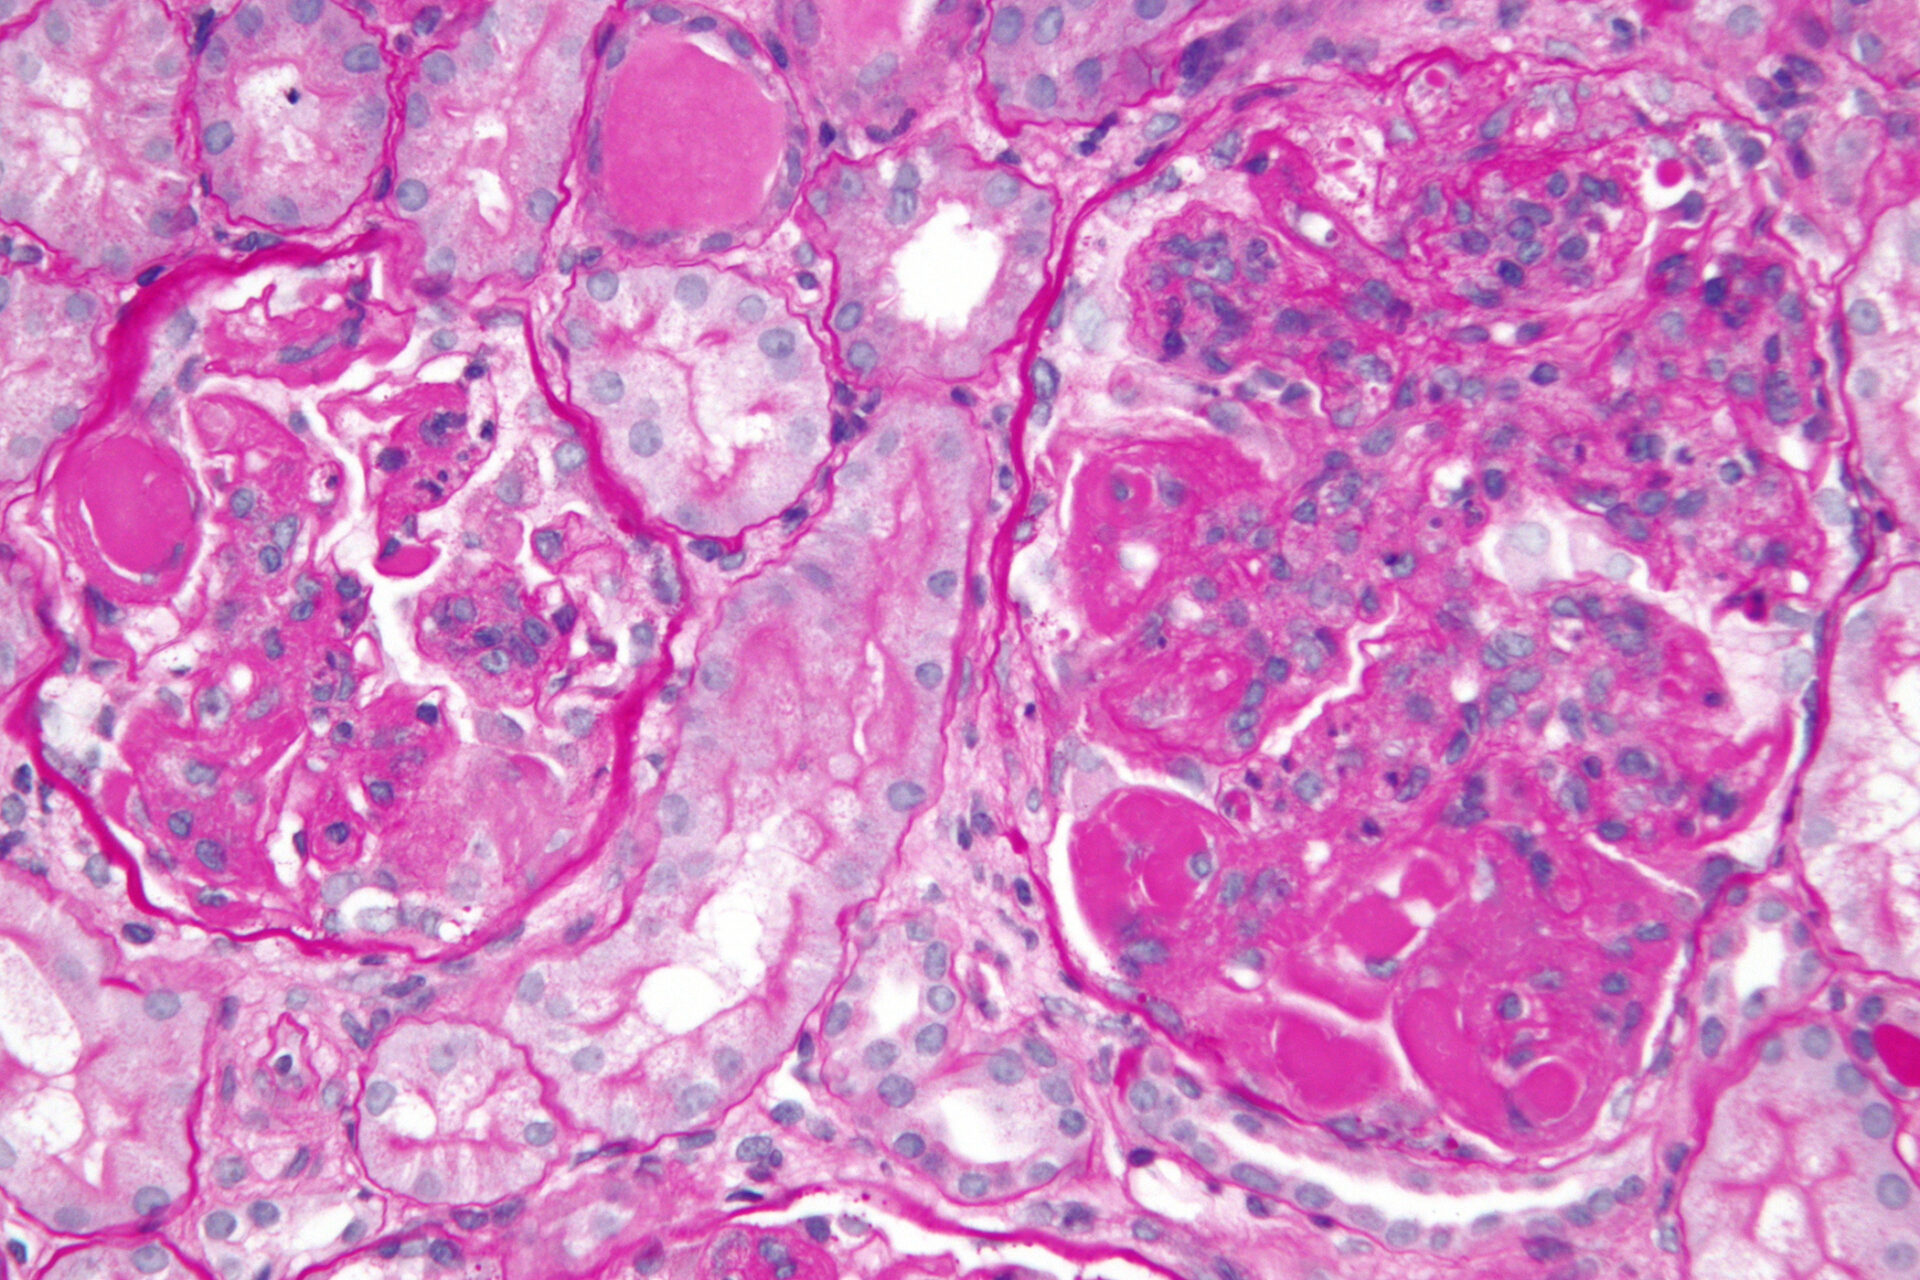

Eine Nierenbeteiligung zählt zu den schwersten Lupus-Formen mit häufig lebensbedrohlichen Verläufen. Um eine Lupus-Nephritis (LN) frühzeitig zu erkennen, wird bei SLE-Patienten mit Auffälligkeiten im Urin eine Nierenbiopsie empfohlen. Die Behandlungsmöglichkeiten haben sich durch die Verfügbarkeit moderner add-on Substanzen verbessert. In der anfangs 2024 erschienenen KDIGO-Leitlinie wird bei LN der Klasse 3 oder 4 eine Kombinationstherapie unter Hinzugabe von Belimumab oder Voclosporin empfohlen. Wobei es wichtig ist, ein evidenzbasiertes Behandlungsschema anzuwenden.